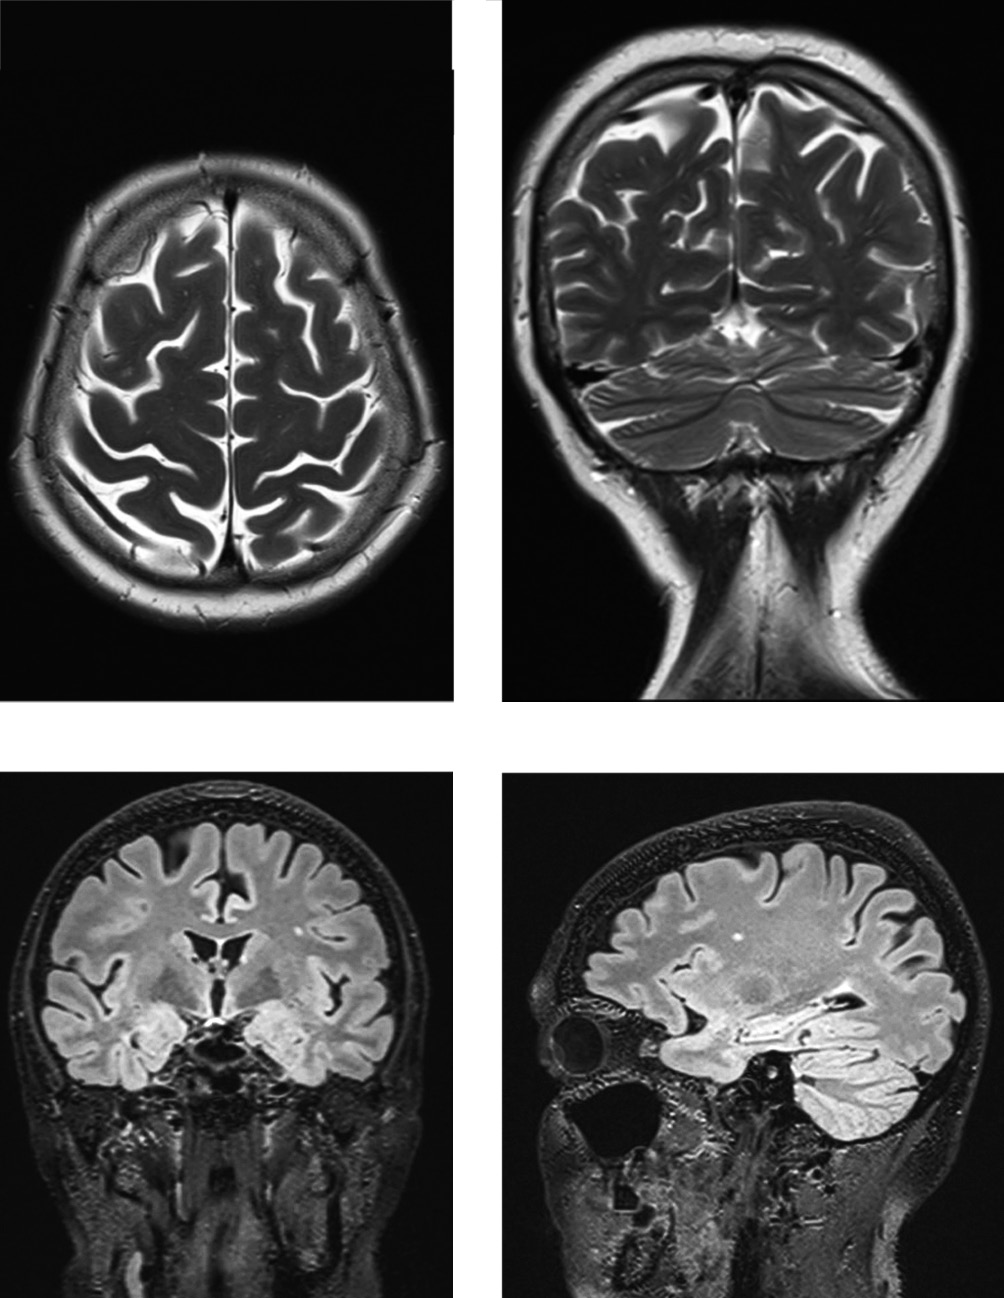

Выполнена магнитно-резонансная томография (МРТ) головного мозга с контрастированием от 13.03.2019. В белом веществе лобных и височных долей, субкортикально и паравентрикулярно — до 10 очагов гиперинтенсивного по T2 и FLAIR сигнала размерами от 0,2 см до 0,6 × 0,3 см и очаги без чётких контуров за счёт перифокального отёка. После введения контрастного вещества сразу и через 20 мин в отсроченную фазу усиления интенсивности сигнала от выявленных очаговых изменений не определяется (рис. 1).

Рис. 1. МРТ головного мозга пациентки С. в режимах T2 (А) и FLAIR (В) от 13.03.2019. / Fig. 1. Brain MRI of patient S. — T2-weighted (A) and FLAIR sequences (B), 13.03.2019.

Повторно была назначена МРТ головного мозга с контрастированием от 10.01.2020 для исключения симптоматики паркинсонизма на фоне демиелинизирующего процесса (рис. 3).

Рис. 3. МРТ головного мозга пациентки С. в режимах Т1 и T2 от 10.01.2020. / Fig. 3. Brain MRI of patient S. — T1-weighted and T2-weighted sequences, 10.01.2020.

На МРТ, взвешенных по Т2: TSE — 3,0 мм в аксиальной проекции, FLAIR FS — 0,9 мм в аксиальной проекции, T13D — 0,9 мм; при DWI и режиме SWI визуализированы суб- и супратенториальные структуры. Срединные структуры не смещены. Дифференцировка серого и белого вещества удовлетворительная. В шишковидной железе имеются мелкие кисты размерами до 0,2–0,3 см. В белом веществе лобных и височных долей, субкортикально и перивентрикулярно — менее 10 очагов гиперинтенсивного по T2 и FLAIR сигнала размерами от 0,2 см до 0,6 × 0,3 см и очаги без чётких контуров за счёт перифокального отека. Боковые желудочки мозга не расширены, симметричные, размер желудочков на уровне отверстий Монро 0,6 см с обеих сторон. III желудочек шириной до 0,5 см. IV желудочек и базальные цистерны не изменены. Хиазмальная область без особенностей. Ткань гипофиза высотой до 5 мм, верхний контур несколько вогнут, МР-сигнал однородный. Супраселлярная цистерна не расширена. Сигнал от зрительных нервов обычный. Слуховые нервы обычной толщины, структура однородная. Субарахноидальные конвекситальные и межгиральные пространства расширены преимущественно в области лобных, теменных долей и сильвиевых щелей на фоне атрофических изменений коры больших полушарий и мозжечка. Миндалины мозжечка расположены на уровне большого затылочного отверстия.

После введения контрастного вещества сразу и через 20 мин в отсроченную фазу усиления интенсивности сигнала от выявленных очагов изменений не определяется.

МР-картина наружной заместительной гидроцефалии. Очаговые изменения вещества головного и спинного мозга демиелинизирующего характера.

Таким образом, по данным МРТ головного мозга с контрастированием, очаги располагаются в субкортикальной и перивентрикулярных областях, очаги демиелинизации не затрагивали структуры экстрапирамидной системы, что исключает непосредственное воздействие очагового демие- линизирующего процесса на синдром паркинсонизма.

Анализ клинического случая показывает, что дебют демие-линизирующего заболевания проявился в возрасте 44 лет. Течение заболевания достаточно мягкое с редкими обострениями, хорошим ответом на терапию глюкокортикостероидными гормонами и удовлетворительным контролем с помощью препарата, изменяющего течение РС. Клиническая картина заболевания обусловлена спинальным поражением при относительно невыраженном демие-линизирующем процессе в головном мозге. Через 17 лет после дебюта заболевания пациентка передвигается самостоятельно. Область базальных ядер, ствола мозга не изменена (рис. 3). БП возникла через 16 лет после дебюта РС. Течение БП более агрессивное, чем РС. Третья стадия БП с моторными проявлениями в виде ригидности и олигобрадикинезии в левой кисти, умеренной постуральной неустойчивостью, камптокормией; и немоторными проявлениями в виде нарушения моторики желудочно-кишечного тракта. Особенностью клинического случая являются раннее появление постуральной неустойчивости, камптокормии и необходимости применения высоких доз леводопы для «включения», что требует дальнейшего динамического наблюдения за пациенткой для исключения дебюта мультисистемной атрофии.

В нашем клиническом случае не было изменения сигнала на МРТ от базальных ганглиев, а также имелся хороший ответ на дофаминергическую терапию, что указывает на сочетание РС и БП у данной пациентки.